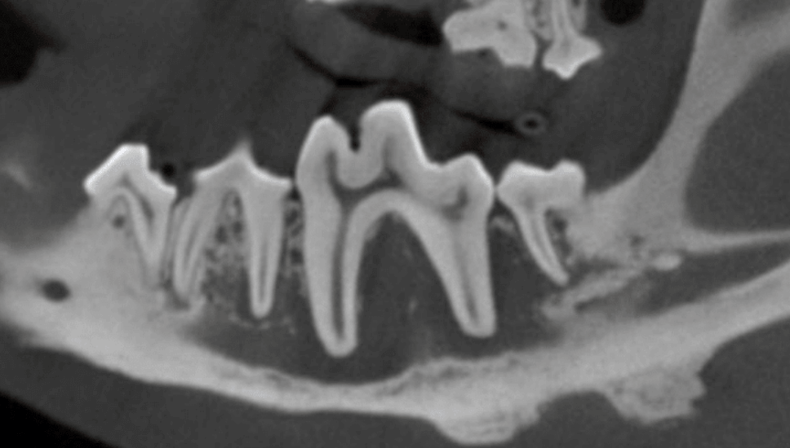

The internal structure of the affected tooth showed disease at the root tips, leading to infection. This infection had spread into the mandibular canal and affected nearby teeth. Although there was reactive bony proliferation on the ventral aspect, significant bone loss was also noted, which posed a risk for a pathological mandibular fracture.

Below: CT Cross Section of Disease